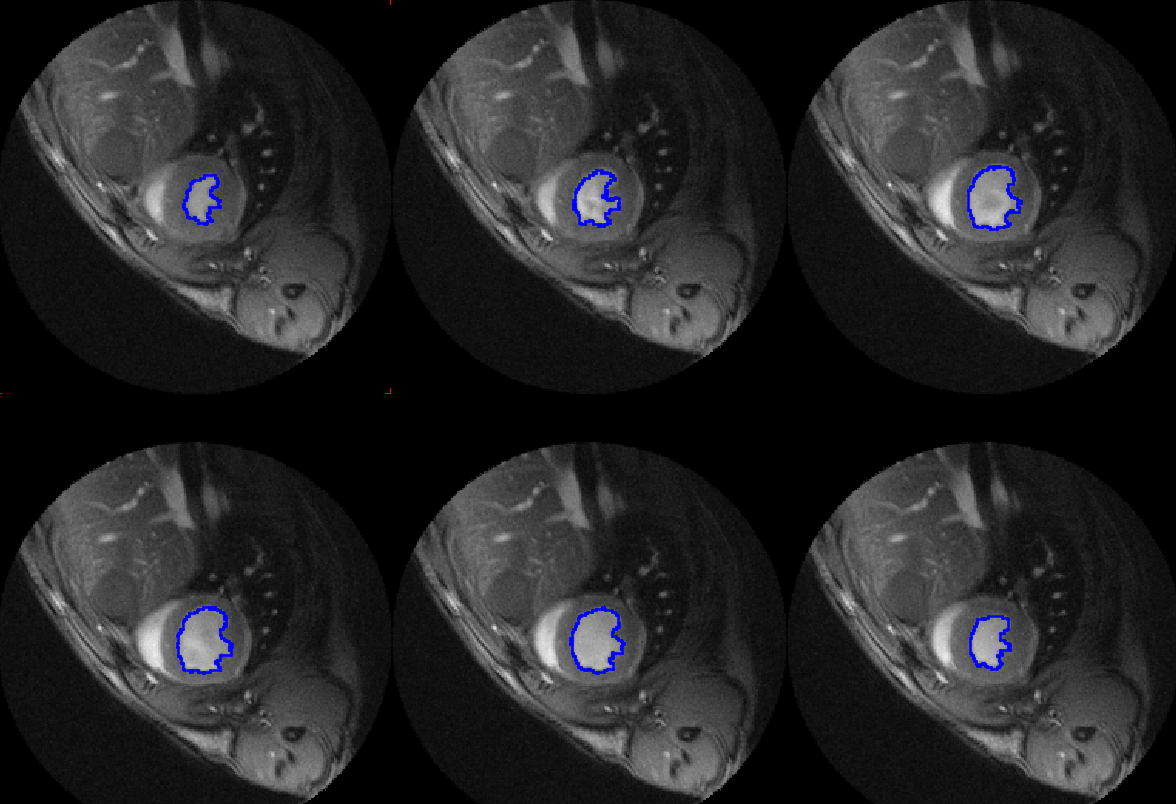

• AI-based segmentation

• Ventricular function